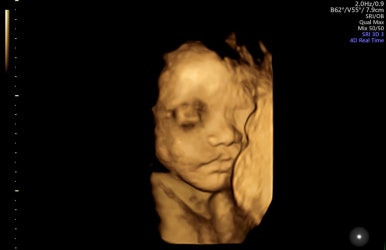

28주 1일

입체초음파로 태아의 얼굴을 볼 수 있는 시기이다!

제일 기다렸던 때이고, 다행히 태아 얼굴을 볼 수 있었다.